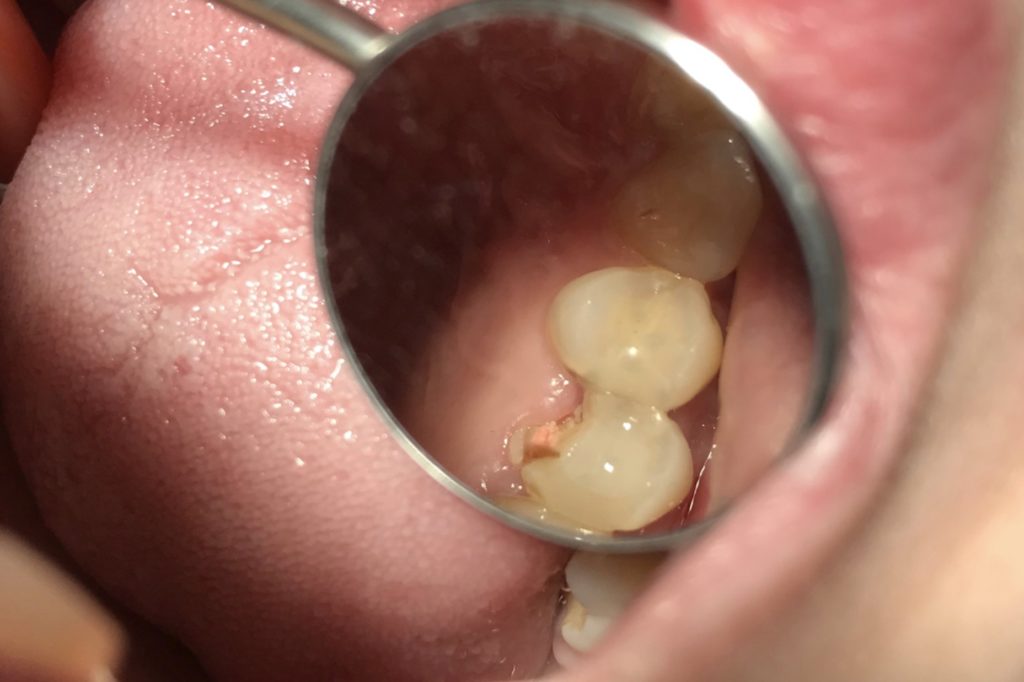

- Прорезывание или сохранение зуба мудрости — косвенной причиной периостита может быть прорезывание восьмых моляров. Почему косвенно? Сама по себе восьмерка не вызывает воспаления, но часто случается, что десневой карман образуется над или за последним прорезавшимся зубом. Туда попадает еда, которую невозможно вынуть. Остатки пищи являются питательной средой для бактерий, вызывающих воспаление кармана, которые могут распространяться на надкостницу, находящуюся в непосредственной близости.